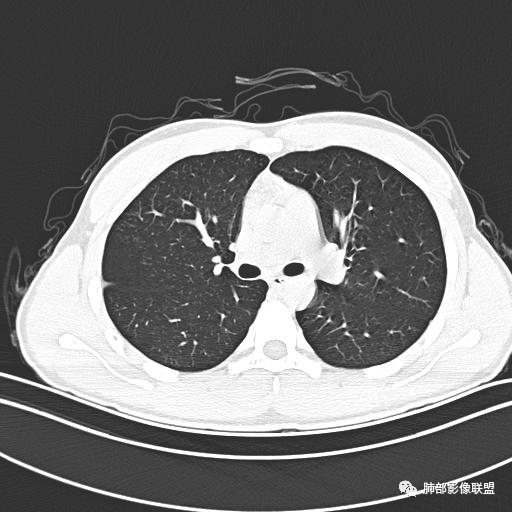

【每日晨读】年轻男性,发热+皮疹+肺内点晕

主  诉:发热、全身皮疹2天。

现病史:患者源于2天前受凉后出现发热,最高体温为38.5℃,且颜面部出现少量皮疹,无鼻塞、流涕、咳嗽、咳痰,未在意而未作特殊处理,次日全身皮疹逐渐增多至全身,伴轻度瘙痒,在当地卫生所给予抗病毒、抗感染治疗(具体用药不详)体温有所下降,但皮疹无明显消退,无腹痛、头痛,食欲无明显减退,为进一步诊治,遂于今日急来我院求治,患者目前精神尚可,体力正常,食欲正常,睡眠正常,体重无明显变化,大便正常,排尿正常。

小强:青年,发热,皮疹;双肺散在结节,周围磨玻璃,点晕征,疱疹病毒感染,鉴别荚膜组织胞浆菌,结核。 大雄:青年,急性起病,发热伴全身皮疹2天,抗病毒治疗体温有下降。双肺随机分布大小不等类圆结节,“点晕征”。考虑水痘-疱疹病毒(VZV)血播询问接触史,查体皮疹分布以及形态基本可诊断。 王开金江津中心医院呼吸科:青年男性,起病急,病程短,以发热,皮疹为首发症状,感染指标以单核细胞升高为主,胸部ct双肺多发结界,周围有晕,点晕表现,随机分布,同意於老师意见,水痘疱疹病毒血流感染累及肺。 王秀仙:双肺多发大小不等结节,周围有晕,边缘模糊,呈点晕征表现。青年,急性起病,发热伴全身皮疹2天,抗病毒治疗体温有下降。考虑疱疹病毒。鉴别荚膜组织胞浆菌。 傅昌瑜:19岁男性,发热、全身皮疹2天,单核细胞增高,双肺多发结节,结节边缘见边界不清磨玻璃影。点晕征+发热、全身皮疹+单核细胞增高——考虑水痘-带状疱疹病毒肺炎。 一切∮随缘:年轻男性,发热,皮疹两天,实验室,CRP,PCT增高,影像:双肺多发散在磨玻璃结节,边界欠清,大小不等,呈点晕征改变,以血管束周围分布为主,局部血管束略增粗,其它无明显改变,考虑:1:病毒性肺炎(水痘疱疹病毒?不知道皮肤有无改变)2:真菌(组织胞浆菌,血管侵袭性肺曲霉)3:GPA4:寄生虫(实验室没有看到嗜酸细胞增高) 赵山河:双肺散在结节,周围有晕,边缘模糊,呈点晕征表现。青年,急性起病,发热伴全身皮疹2天,抗病毒治疗体温有下降。考虑水痘—疱疹病毒感染。洪桥爱:青年男性,发热、皮疹2天,伴瘙痒,皮疹于面部首发,之后进展至全身,虽然没有对皮疹进行描述,但是从出疹时间及皮疹进展情况,伴瘙痒,应该就是个水痘患者;CT提示双肺随机分布结节影,部分结节伴有边界不清晕征,考虑水痘血播肺。 刘强:年轻男性,急性起病,皮疹,发热,抗感染治疗体温下降,说明有效。影像表现为散在点晕征,感染类疾病谱(疱疹病毒,真菌,结核),结合年龄,皮肤皮疹,考虑水痘-疱疹病毒性肺炎。 小兜:男性,19岁,发热皮疹两天,颜面部至全身,CRP,降钙素及单核增高。CT示双肺散在小结节,周围伴磨玻璃影,点晕征,考虑为水痘-带状疱疹病毒(varicella-zoster virus,VZV)肺炎 必有路:青年,皮疹+发热+“点晕征”→水痘-疱疹病毒(VZV) 许慧良:青年男性患者,发热、皮疹2天,体温最高38.5℃,第3天皮疹扩展至全身,伴瘙痒,胸部CT:双肺多发随机分布的小结节,结节周边见边界模糊的晕征,考虑水痘病毒感染流心明智:男,19,急性起病,发热伴全身皮疹2天。出疹顺序头→全身,抗病毒有效。胸部CT:两肺多发大小不等类圆形实性小结节影,随机分布,结节周围环绕GGO,边界模糊,呈点晕征。出疹特点是关键,未提示。考虑:血播病毒性肺炎,水痘-疱疹病毒?麻疹?鉴别荚膜组织胞浆菌、TB、血管炎、寄生虫等。 浪迹天涯:病灶多为5-10mm大小结节,结节周围可见磨玻璃样的晕环,常多发,可分布于肺内任何区域,考虑水痘—带状疱疹病肺炎如果短时间内有新的一个区域浸润,更加能说明,

知识拓展--点晕征疾病普

1. 肿瘤:血管原发肿瘤:血管肉瘤(右房)、上皮样血管内皮瘤、血管内淋巴瘤(大B)转移瘤:消化道、生殖道转移,关注绒癌、恶黑及结肠癌

2.感染:真菌:荚膜组织胞浆菌。病毒:疱疹病毒。结核。

3.血管炎。4.寄生虫病。5.PCH/PVOD。